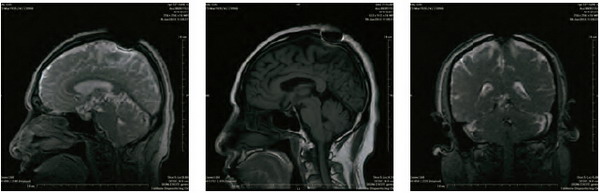

開初仁波且MRI核磁共振腦斷層掃描醫學圖片

這是開初仁波且修金剛換體禪後,在加州醫療中心檢查身體時拍攝的MRI核磁共振檢測照片。可以清晰看見開頂後,頭頂大樂輪門處頭骨、皮肉等大開,開口寬約兩英寸,腦髓開出雞蛋大的凹洞。更令人震撼的是,當開初仁波且拍攝掃描照片時,整塊頭骨突然不見,而呈現出彌勒菩薩乳胎嬰童像,身搭俱袍,手腳呈現,心空大洞,跏趺而坐,在電腦上清晰可見五官面容,眼睛、鼻子、嘴巴。